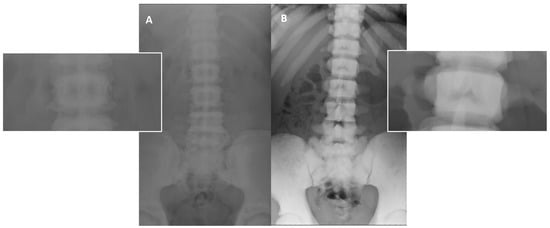

(1) Diffuse increased bone density, sclerosis involving the skull, spine, pelvis, and appendicular bones: This sign is the most known and recognized imaging feature of osteopetrosis, and the reason for the name ‘marble bone disease’ of this condition. Diffuse bone sclerosis can be found in all subtypes of osteopetrosis (ADO, ARO, IAO), even if with slightly different patterns and skeletal locations; particularly in the ARO type, the bone sclerosis can be so marked to assume the so-called ‘marble bone’ appearance (Figure 1).

Figure 1. (A) conventional radiography of the chest of a young healthy female (shown as comparison). (B) conventional radiography of the chest in a 29-year-old female diagnosed with osteopetrosis (clinical and radiological diagnosis in absence of a pathogenic variant in osteopetrosis-related genes). All the skeletal segments included are affected by diffuse and markedly increased bone density (spine, ribs, clavicle, scapulae, humerus): ‘Marble bone’ appearance.